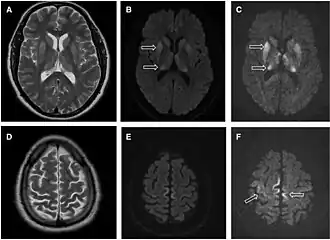

- MRI with diffusion weighted inversion (DWI) and fluid-attenuated inversion recovery (FLAIR) shows a high signal intensity in certain parts of the cortex (a cortical ribboning appearance), the basal ganglia, and the thalami.[42] The most common presenting patterns are simultaneous involvement of the cortex and striatum (60% of cases), cortical involvement without the striatum (30%), thalamus (21%), cerebellum (8%) and striatum without cortical involvement (7%). In populations with a rapidly progressive dementia (early in the disease process), MRI has a sensitivity of 91% and specificity of 97% for diagnosing CJD.[46] The MRI changes characteristic of CJD may also be seen in the immediate aftermath (hours after the event) of autoimmune encephalitis or focal seizures.[42]

Imaging of the brain may be performed during medical evaluation, both to rule out other causes and to obtain supportive evidence for diagnosis. Imaging findings are variable in their appearance and also variable in sensitivity and specificity.[49] While imaging plays a lesser role in diagnosis of CJD,[50] characteristic findings on brain MRI in some cases may precede onset of clinical manifestations.[51]

Brain MRI is the most useful imaging modality for changes related to CJD. Of the MRI sequences, diffuse-weighted imaging sequences are most sensitive.[52] Characteristic findings are as follows:

- Focal or diffuse diffusion-restriction involving the cerebral cortex or basal ganglia. The most characteristic and striking cortical abnormality has been called "cortical ribboning" or "cortical ribbon sign" due to hyperintensities resembling ribbons appearing in the cortex on MRI.[53] The involvement of the thalamus can be found in sCJD, is even stronger and constant in vCJD.[54]

- Varying degree of symmetric T2 hyperintense signal changes in the basal ganglia (i.e., caudate and putamen), and to a lesser extent globus pallidus and occipital cortex.[50]